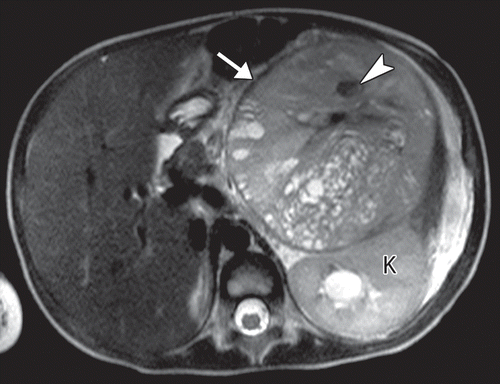

Nephroblastomatosis

Picture of nephroblstomatosis + Wilms

Screening ultrasound every 3 months until patient turn 8